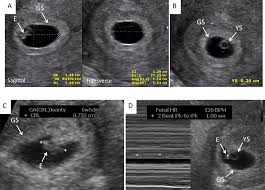

Your partner to ask any questions he may have, get to know your healthcare provider, hear the heartbeat, and see the baby via ultrasound. 10 week pregnant ultrasound can determine the exact site of pregnancy and if there is ectopic pregnancy it can be diagnosed. At 10 weeks pregnant, you're getting close to the end of your first trimester. 10 weeks 3 days pregnant. A month later hemmorage healed on it own and was back to normal activity.

You may be wondering when those pesky early pregnancy symptoms will start to fade or getting ready to share your big news with the world. This device is kind of like a microphone placed on the belly. Pregnancy symptoms & belly pictures. But if you are feeling some uncomfortable symptoms, things may seem like they're dragging. Ultrasounds are usually done in the first trimester to confirm a viable pregnancy, confirm the heartbeat, and confirm molar or ectopic pregnancies and also to assess abnormal gestation. A month later hemmorage healed on it own and was back to normal activity. 10 weeks 3 days pregnant. Ultrasound image of identical twins at 10 weeks, these babies share the same sac. By conducting a scan, she will be able to identify whether or not your baby is developing normally. Avoid wearing tight and constricting clothes. Pregnancy week 10 learn what is happening with your baby's development in week 10. His toes and fingers have taken a distinct form and started developing fingernails as well. At 10 weeks of pregnancy, the foetus weighs about 4gm and measures around 3.1cm from crown to rump.

At this stage, the baby is growing even more rapidly! Your baby at 10 week pregnant has started developing tissue and you can see his arms and legs forming. Expansion of the uterus, muscles and ligaments to accommodate a growing baby are all part of the growing bump. Ultrasound image of fraternal twins at 10 weeks, you can see the thick membrane separating the babies. Fetus measured at 10 weeks 4 days and all looks good for now :) violation reported. Bloating can still be a contributor to a perceived bump and not everyone will see a baby bump at 10 weeks. At 10 weeks pregnant, you're getting close to the end of your first trimester. Check baby fetal development signs, baby movement, nutrition, diet suggestions. At 10 weeks of pregnancy, the foetus weighs about 4gm and measures around 3.1cm from crown to rump. Pregnancy week 10 learn what is happening with your baby's development in week 10. Learn about being 10 weeks pregnant. Blood tests aren't generally necessary during early pregnancy except as a tool to determine what sort of care you might need. Those cells are tested for genetic abnormalities.